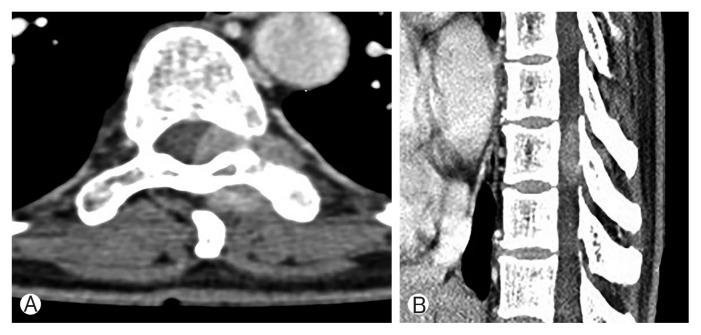

A 54-year-old woman visited Gangnam Severance Hospital for left side flank pain. She had a history of total removal of malignant melanoma on the left eye ball 20 years prior. No evaluation had been performed since then. A paravertebral mass at thoracic ninth level (T9) was discovered on spinal magnetic resonance imaging, and pathology confirmed malignant melanoma. Following positron emission tomography-computed tomography, no other metastasis was discovered. After removal of the paravertebral mass, palliative chemotherapy (dacabarzine + tamoxifene) was administered in 3 cycles over 2 months. Radiotherapy with simultaneous integrated boost technique was performed at 4,350 cGy total over 15 days, 290 cGy per delivery, and was administered with the first cycle of palliative chemotherapy. Despite this treatment, multiple metastases developed throughout her body 7 months later, and the patient is continuing chemotherapy.

一名54岁女性因左侧胁腹疼痛就诊于江南severance医院。她20年前有左眼恶性黑色素瘤全切病史,此后未进行过评估。脊柱磁共振成像发现胸9(T9)水平的椎旁肿块,病理证实为恶性黑色素瘤。正电子发射断层扫描-计算机断层扫描检查后,未发现其他转移灶。切除椎旁肿块后,在2个月内分3个周期给予姑息化疗(达卡巴嗪+他莫昔芬)。采用同步整合增量技术进行放疗,15天内总剂量达4350 cGy,每次290 cGy,与第一个周期的姑息化疗同时进行。尽管进行了这种治疗,但7个月后患者全身出现多处转移,目前仍在继续化疗。